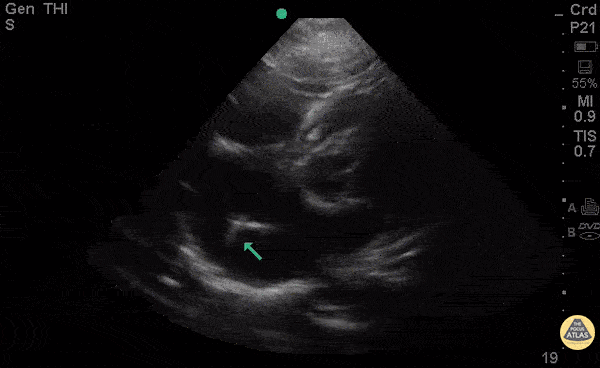

35 y/o M PMH truncus arteriosus s/p multiple surgeries, bioprosthetic aortic valve, AICD, and recent treatment for endocarditis presents with rectal bleeding and syncope in setting of warfarin use for his chronic DVTs. INR was found to be 1.0. POCUS with pacemaker leads with possible clot vs vegetation attached to the tip. Concern for thrombus given pt's normal INR vs possible infected pacemaker vegetation. Dr. Bryan Jarrett - Kings County Emergency Medicine